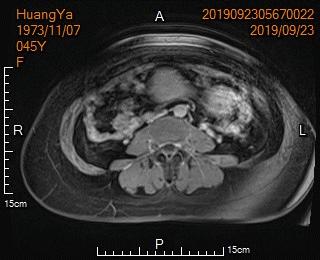

中年女性,发现子宫肌瘤进行性增大5年余。复查彩超提示多发肌瘤,较前明显增大(最大者直径近10cm)。近半年尿频、尿急症状进行性加重,考虑增大的子宫肌瘤压迫膀胱所致。

- 盆腔磁共振检查显示显示多发子巨大宫肌瘤,压迫膀胱

MRI显示多发子巨大宫肌瘤,压迫膀胱

MRI显示子宫多发巨大肌瘤